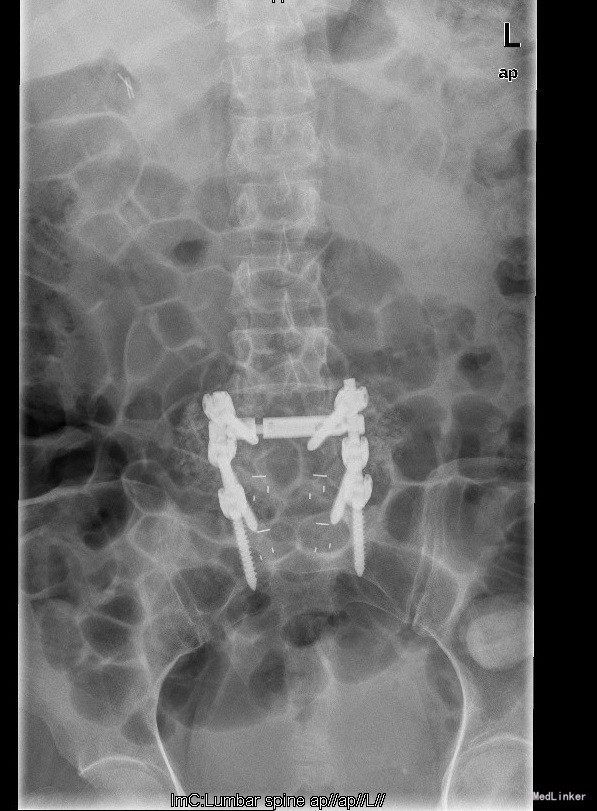

诊断:腰4椎II°滑脱症,腰5椎I°滑脱症 治疗:经后路腰4、5椎切开复位、椎管减压、Capstone椎间及后外侧人工骨+自体骨植骨融合、Legacy内固定术